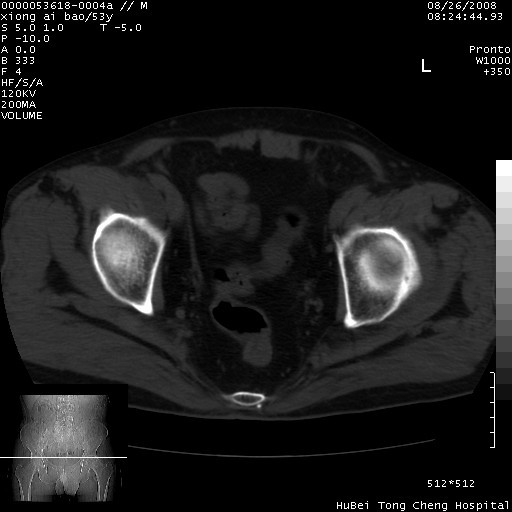

标题: CT15583:M,53Y。请老师指教分析骨盆及其他病变。 [打印本页]

标题: CT15583:M,53Y。请老师指教分析骨盆及其他病变。

股骨头坏死/腹股沟疝。

双侧股骨头无菌坏死,左侧腹股沟斜疝。

非常典型病例,双侧股骨头坏死伴双髋关节周围软组织肿胀,左腹股沟疝。

双侧股骨头坏死伴双髋关节周围软组织肿胀,左腹股沟疝。

双侧骨股头无菌性坏死,左侧腹股沟疝

双侧髋关节肿胀明显,感觉还不能排除结核。

考虑双侧髋关节结核,左侧腹股沟疝